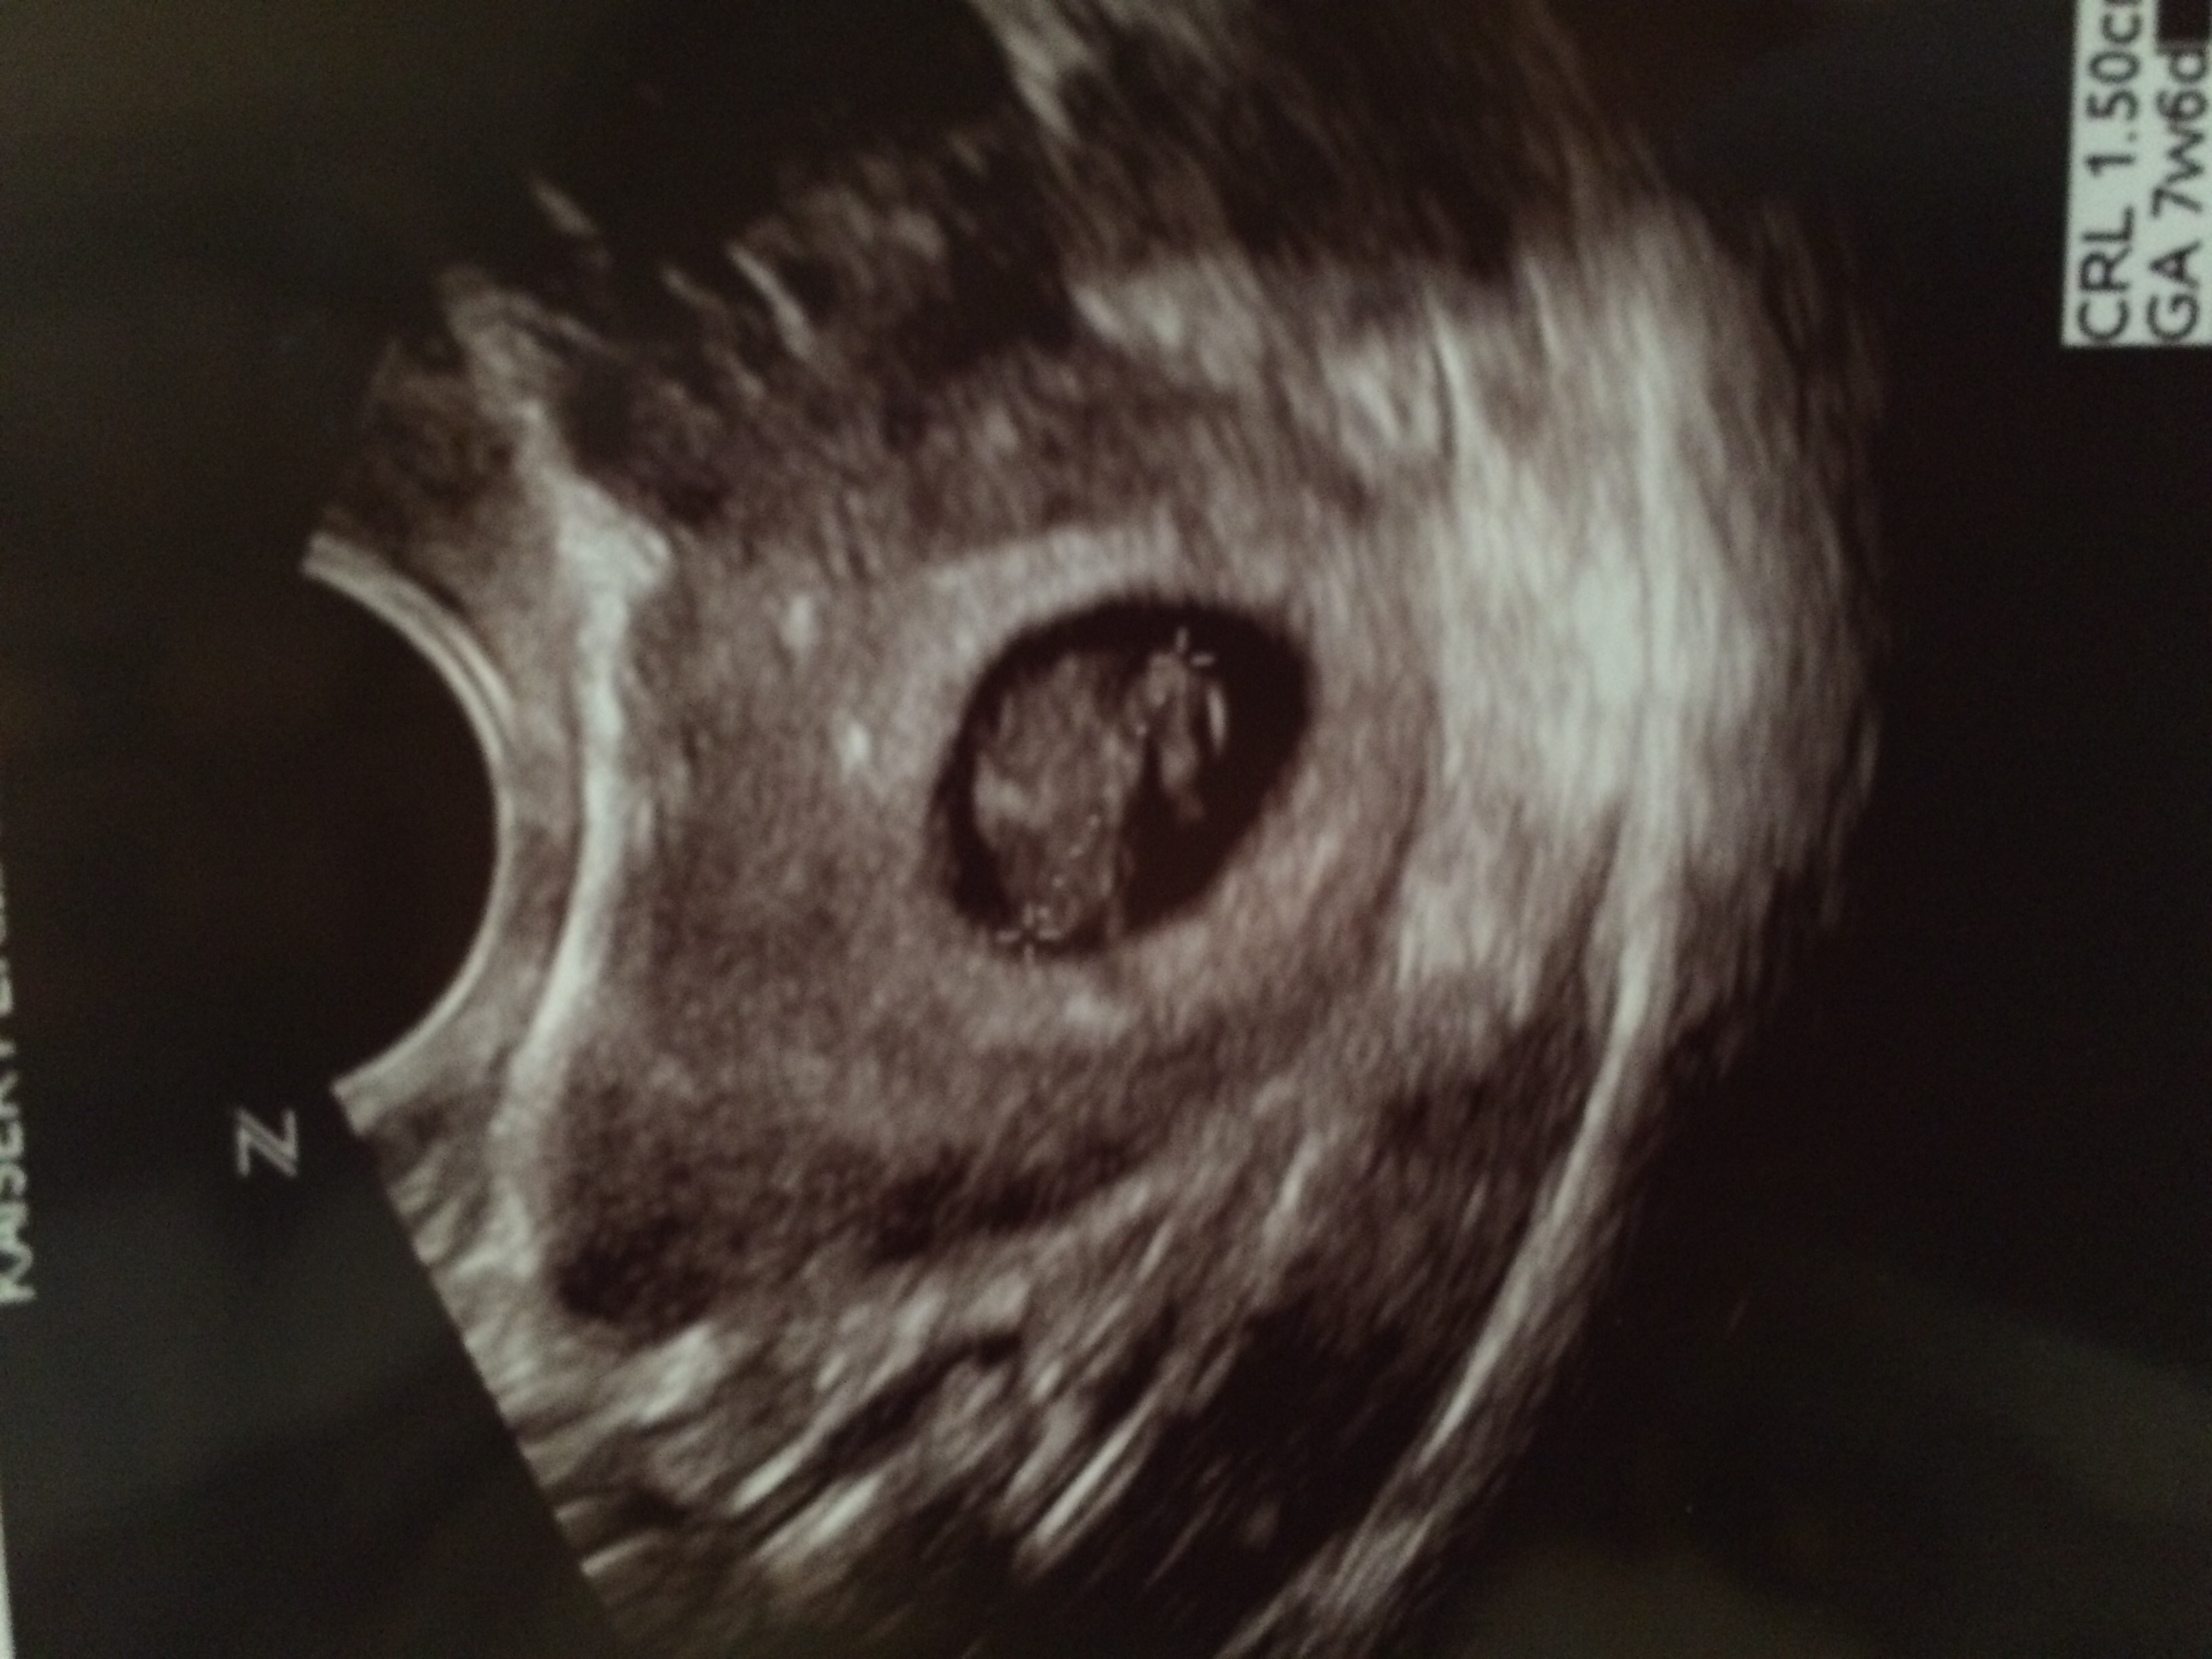

• I had my first ultrasound this morning.  Baby measured at 7w2d and had a heart rate of 145 bpm :)

BFP #1: 12/29/14 | EDD: 9/9/15

image